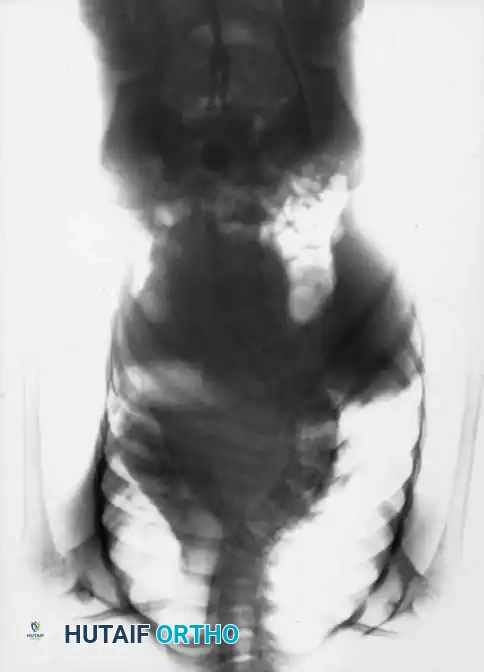

The Cobb angle is the gold standard for quantifying the magnitude of the coronal deformity. It is measured by drawing lines parallel to the superior endplate of the most tilted cephalad vertebra and the inferior endplate of the most tilted caudal vertebra.

Fig. 11: Measurement of the Cobb angle on a standing PA radiograph.